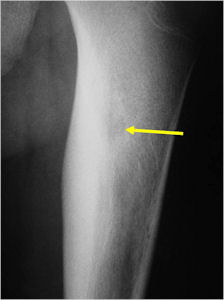

Plain X-Rays:

- Lucent nidus surrounded by a zone of marked sclerosis

- The nidus may demonstrate mineralization/ossification usually from the center outward that appears as a central zone of density within the nidus

- Periosteal bone is solid, rarely lamellated

- Cortical and subperiosteal osteoid osteomas are usually associated with much more reactive sclerosis than medullary tumors

- The periosteal reaction is continuous and often appears as cortical thickening (benign appearing reaction)